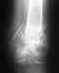

После ДТП 3.07.2005 диагноз: кососпиральный оскольчатый перелом нижней трети плеча. Операция накостноко остеосинтеза была 13.07.2005 - пластина и 5 шурупов.Вопрос такой: прошло 3 недели после операции, можно ли снять гипсовую лангету и соблюдая осторожность начинать сгибать/разгибать руку без нагрузок? Дело в том что после месяца в гипсе локоть уже не сгибается т.к тянуться связки и мышцы. Я боюсь что если проведу еще месяц в гипсе то потом функции локтя будут очень долго восстанавливаться. Есть ли какие-нибудь рекомендации для скорейшего восстановления?